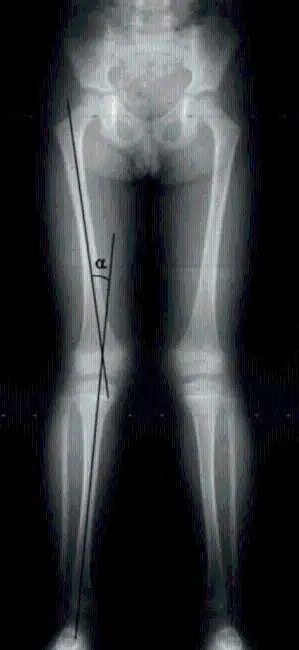

“X型腿”其實(shí)是一種狀態(tài)。當(dāng)我們用肉眼觀察時(shí),站立時(shí)我們的腿呈X形。

膝外翻是X形腿的真正醫(yī)學(xué)名稱(chēng)。站立時(shí),如果膝蓋并攏而腳踝不能并攏,這就是膝蓋外翻。